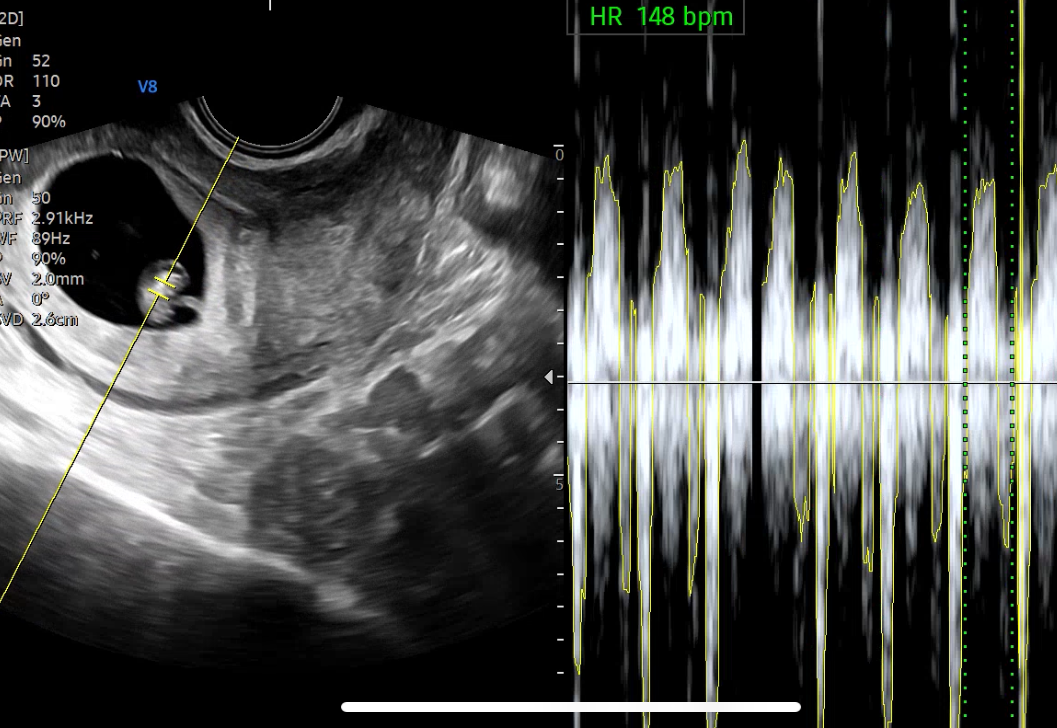

2주 동안 무럭무럭 자라서 조금 커진 아기집도 보이고 안에는 태아와 탯줄도 보였어요.

심장소리도 듣고 왔어요. 심장 박동수는 148 bpm 정상이라고 하셔서 잘 크고 있구나 싶어 기특했습니다.

(벌써부터 남편은 심장소리가 남자애 같다 어쩐다.. 아직 설레발은 금지)